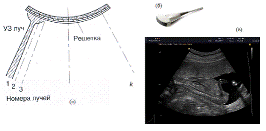

На рисунке 17 показана

первичная конструкция устройства генерации вибрации. Два вибратора совместно

генерируют механические колебания в ткани, и прилагаемый ультразвуковой датчик

регистрирует движение тканей. Как уже было сказано ранее, ответная реакция

ткани на возмущение вибратором может вызвать нежелательные вибрации у самого

датчика. Соответственно эти колебания должны быть сведены к минимуму, как для

поддержания удобства исследования оператора, так и точности электронных

вычислений при построении эластограммы. Виброэластограмма может быть выполнена

при колебаниях с частотой 5-25 Гц, в течение трех секунд [Hassan Rivaz et al.].

Однако, для достижения большей точности, он выполнял измерения на более длинном

интервале времени - 10 с.

Рис. 17. Первичная

конструкция датчика и генератора вибрации